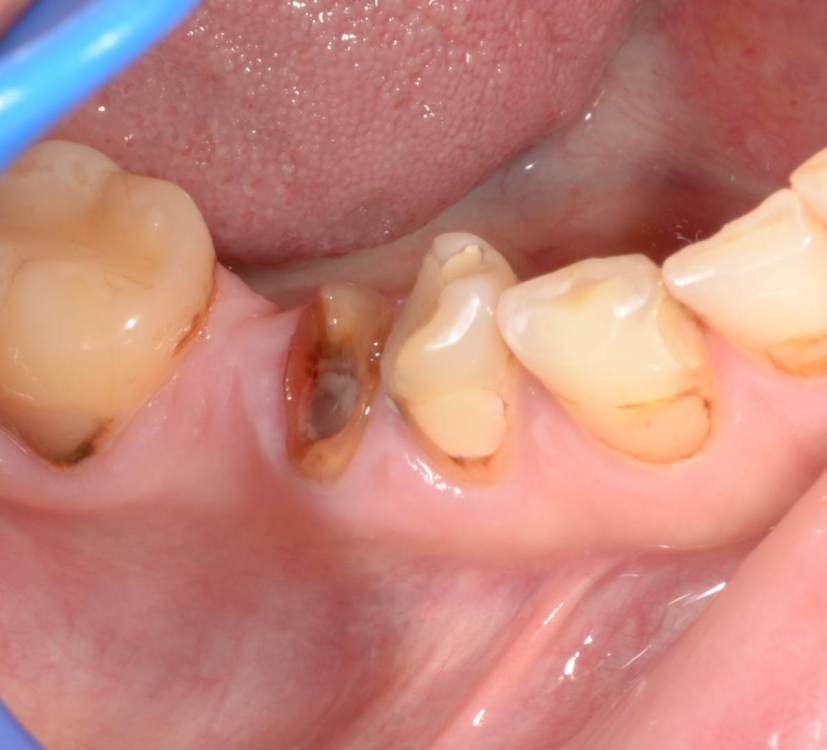

Большой Зеленый Опубликовано 27 мая, 2022 Поделиться Опубликовано 27 мая, 2022 Через 9 лет. Есть немного рецессии.. 2 Ссылка на комментарий

pit Опубликовано 27 мая, 2022 Поделиться Опубликовано 27 мая, 2022 4 часа назад, Большой Зеленый сказал: Через 9 лет. Есть немного рецессии.. Это связано исключительно с вестибулярной позицией импланта. Это как раз к вопросу про те минимальные 2мм до вестиболярной стенки, вне зависимости есть она или ты ее создаешь. Ссылка на комментарий

Большой Зеленый Опубликовано 27 мая, 2022 Поделиться Опубликовано 27 мая, 2022 4 часа назад, pit сказал: Это связано исключительно с вестибулярной позицией импланта. Это как раз к вопросу про те минимальные 2мм до вестиболярной стенки, вне зависимости есть она или ты ее создаешь. С тех пор я стал хитрее умнее и опытнее ))) 1 час назад, alboard сказал: А в чем смысл ее сохранности, если препарируя под имплантат вы все равно ее в большинстве случаев сносите? Первичная стабильность импланта зачастую достигается только перегородкой.. Ссылка на комментарий

Большой Зеленый Опубликовано 28 мая, 2022 Поделиться Опубликовано 28 мая, 2022 12 часов назад, Женька сказал: @Большой Зеленый это вроде ваш старый кейс? напомните пожалуйста, тут присыпка+мембранинг вестибулярно и вестибулярным лоскутом слегка послабленным всё закрыли? Да все так и есть как Вы и описали. Работе почти 10 лет. Присыпка мп3 от остеобила сверху "ильгамовская" губка . Считаю что результат вполне удовлетворительный. Рецессия обусловлена как уже сказали выше вестибулярным положением импланта ,ну и недозаглублен чуток. Ссылка на комментарий